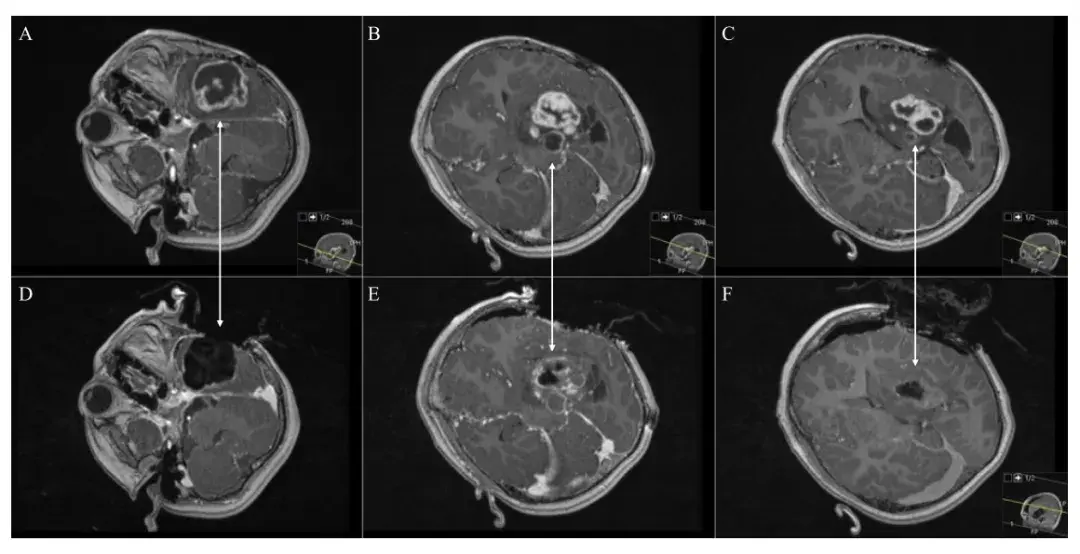

一边手术,一边完成磁共振检查 6岁孩子患有左颞岛叶胶质母细胞瘤,为了尽可能地完整切除肿瘤,确保没有残余,术者使用术中核磁设备(iMRI)。术中核磁(iMRI)一般采用移动式磁体,允许...